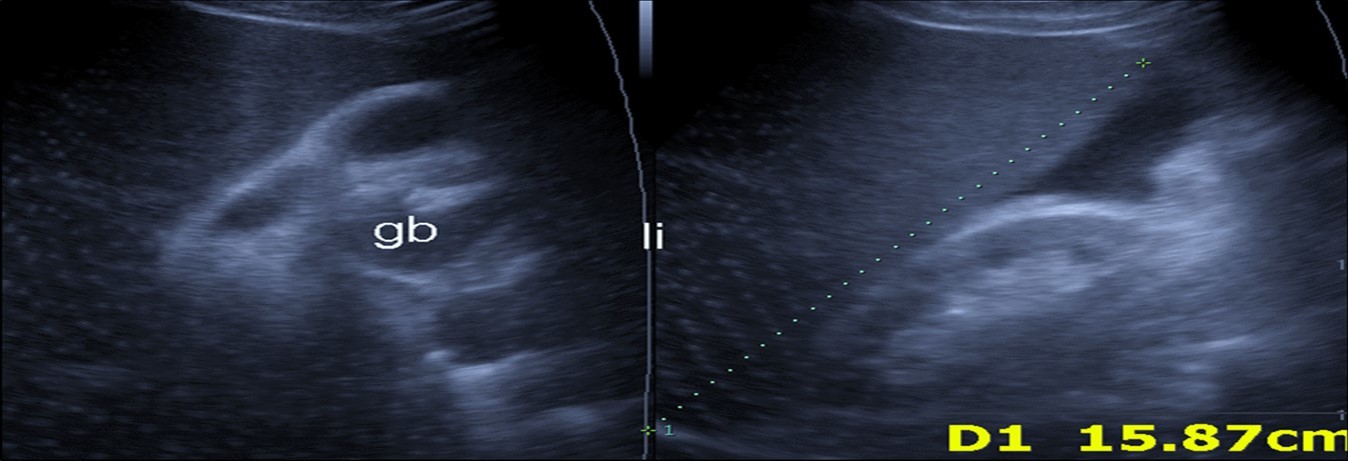

Abdominal ultrasound may revealed any of the followings:-Mild hepatomegaly with echogenic parenchyma and ascites in cases with hepatic impairment (Figure 4, Figure 5) ,thick walls of gall bladder with mildly dilated Common bile duct suggesting of biliary stasis and cholecystitis (Figure 6) .Abnormal renal echogenicity (Figure 7), suprarenal gland enlargements with heterogeneous texture ,splenic wedge shape area of hypoechogenicity ,thickened walls of bowel mainly the rectosigmoid region ,dilated bowel loops with free peritoneal fluid, and gases in the bowel wall with mesenteric and portal vein gases suggesting of bowel wall infarction13.

Figure 5.Real time ultrasound showing mild hepatomegaly (li), ascites and thickened gall bladder wall(gb).

Figure 6.Real time ultrasound showing free ascites (asc) in patient with Covid-19.